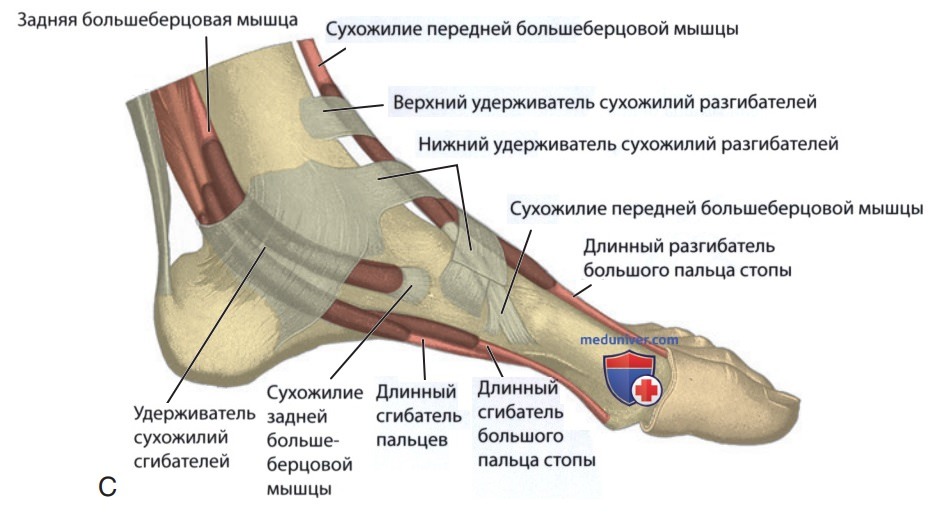

Анатомические фото голеностопного сустава и его суставных поверхностей